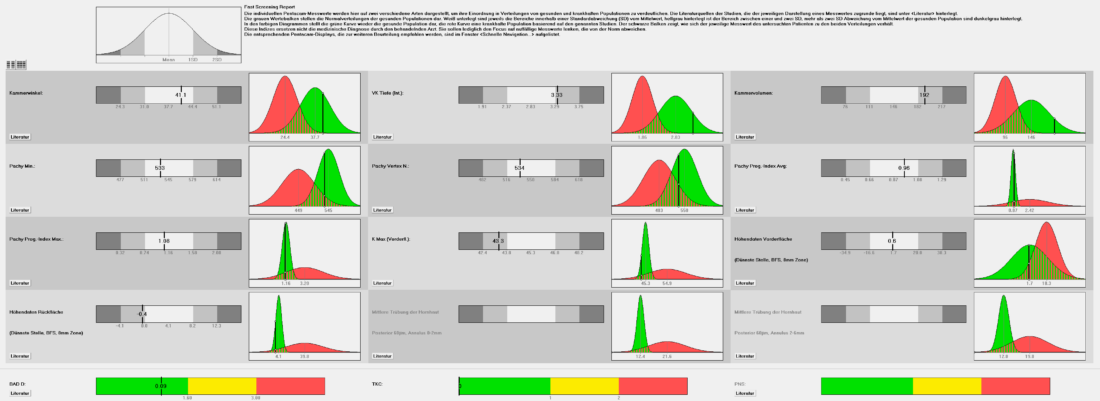

Die Augen Vorsorge Untersuchung heisst bei uns „Panorama Check“, weil unter anderem mit einer Ultra-Weitwinkel Kamera die Netzhaut abgebildet wird. Dazu wird das Auge sorgfältig von vorne bis hinten angeschaut. Besonderer Fokus wird gelegt auf die Netzhaut mit dem Sehnerv und der Makula, aber auch die Augenlinse, die Vorderkammer, die für die Regulierung des Augendruckes wichtig ist. In der heutigen Zeit mit intensiver Bildschirmnutzung wird aber auch der Tränenfilm, die Schleimhaut und die Hornhaut kurz angeschaut. Zudem erfolgen Funktionsteste, um gröbere Auffälligkeiten in der Augenbeweglichkeit oder Pupillenreaktion festzustellen.

Der Augendruck selbst wurde früher als sehr wichtig angeschaut. Er dient zwar auch heute noch als Faktor in der Erkennung, Diagnose und Behandlung eines Glaukoms (eines grünen Stars). Das Verständnis der Krankheit Glaukom hat sich aber grundlegend geändert, da viele Betroffene ein sogenanntes Normaldruckglaukom haben, während andere resilient sind und trotz zu hohem Druck nie einen degenerativen Schaden entwickeln.

Der Augendruck ist also nur eines der Puzzleteile. Nachfolgend sehen Sie Aufnahmen wie sie bei uns im Rahmen eines „Panorama Check“ entstehen.